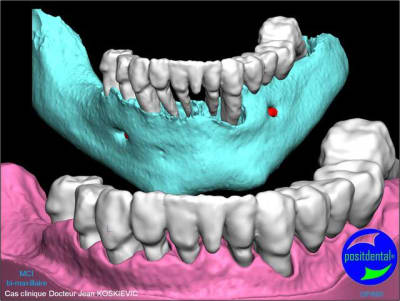

Extractions MCI en 1 chirurgie

gestion des artéfacts en présence de couronnes

chirurgie à venir

3D maxillaire inférieur et photo